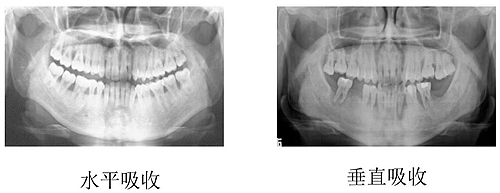

在牙周炎時(shí),同一牙的不同部位和牙面,可以存在不同形式和不同程度的牙槽骨吸收,可表現(xiàn)為一下幾種形式。

(一) 水平型吸收

是最常見(jiàn)的吸收方式。牙槽間隔、唇舌側(cè)或舌側(cè)的嵴頂邊緣呈水平吸收,而使牙槽嵴高度降低,通常形成骨上袋。

(二) 垂直型吸收

也稱(chēng)角形吸收,指牙槽骨發(fā)生垂直方向或斜行的吸收,與牙根面之間形成一定角度的骨缺損,牙槽骨高度降低不多,而牙根周?chē)俏蛰^多。大多形成骨下袋,最常見(jiàn)于鄰面。根據(jù)骨質(zhì)破壞后剩余的骨壁數(shù)目,骨下袋可分為一壁骨袋、二壁骨袋、三壁骨袋、四壁骨袋、混合骨袋。

牙槽骨吸收的方式和程度,可通過(guò)X線片來(lái)觀察。正常情況下,牙槽嵴頂?shù)接匝拦琴|(zhì)界的距離約為1~2mm,若超過(guò)2mm則可視為牙槽骨吸收。牙周炎的骨吸收最初表現(xiàn)為牙槽嵴頂?shù)挠补虐逑?,或嵴頂模糊呈蟲(chóng)蝕狀。